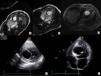

The patient was asymptomatic and underwent routine exams, including an electrocardiogram which revealed nonspecific abnormalities due to which he was referred for a transthoracic echocardiogram (TTE). This showed an intracardiac cystic mass. A transesophageal echocardiogram (TEE) and additional blood tests were performed. The latter only revealed eosinophilia of 3.1%, while the former confirmed the presence of a cystic mass with a diameter of 4.5 cm located in the interventricular septum, protruding into the left ventricular outflow tract and extending to 1 cm below the aortic valve, with associated septal hypokinesia, and without continuity with the cardiac chambers. A bicuspid aortic valve with moderate aortic regurgitation and a dilated ascending aorta were also observed. Magnetic resonance imaging (MRI) showed the mass to be hyperintense in T2, revealed moderate aortic regurgitation and confirmed the other echocardiographic findings (Figure 1). The patient was asymptomatic.

The patient underwent surgery, the cyst being excised through enucleation by blunt dissection with (at times unsuccessful) attempts to preserve the capsule (Figure 2A-C) plus aortic valve replacement with a mechanical valve (27 mm St. Jude Medical Regent®). The ascending proximal aorta and the aortic root (noncoronary sinus) were replaced with a 28 mm Gelseal® graft by a modified Bentall procedure. There were no complications during surgery. The postoperative echocardiogram showed that the inferior part of the septum was thin and dyskinetic, but there were no other abnormalities. The patient was discharged 10 days after surgery (Figure 2D-E).

(A-C): Images captured during surgical resection of the cyst. (A): Cyst causing bulging of the interventricular septum and protruding into the left ventricular outflow tract; (B): intramyocardial location of the cyst; (C): cyst rupture and flow of clear fluid; (D and E): transthoracic echocardiogram after surgery showing a thin interventricular septum and delineation of the previous location of the cyst; (F and G): microscopic aspects of the cyst: (F): cyst wall, H & E stain ×100; (G): cytokeratin 5/6 ×400 (left) and vimentin ×400 (right): keratin and vimentin co-expression by the cells of the internal layer of the cyst. RE: internal cell layer of the cyst; F: fibrosis; M: myocardium.

Pathological examination of the cyst revealed that macroscopically it was a cystic formation 4 cm in its largest diameter and microscopically a cyst with a sheath composed of a single cell layer, positive for keratin and vimentin. The wall was thin and fibrous with focal and scattered calcifications and in continuity with the adjacent myocardium. The diagnosis was a simple mesothelial pericardial cyst (Figure 2F-G).